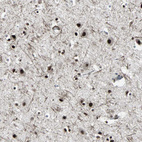

Immunohistochemical staining of human bone marrow shows strong nuclear positivity in hematopoietic cells.